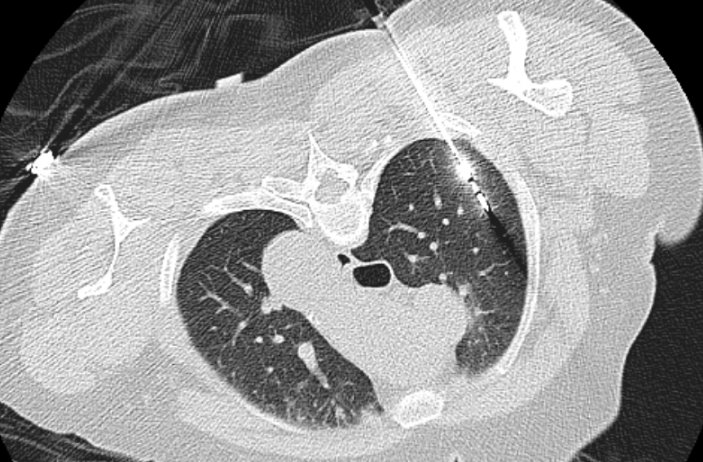

当天,心胸外科主任阳诺带领消融团队开展手术。他介绍,在术前,穿刺手术机器人系统基于患者 CT 影像,能自动构建详细的肺部 3D 立体模型, 清晰呈现结节与周围血管、气管等重要组织的位置关系。

「它就像一位『智能导航员」,精准规划穿刺路径、角度与深度,有效避开血管、气管等重要组织结构,将误差控制在毫米级。」阳诺说。

术中,机器人就像有了「智慧眼睛」和「稳定双手」,整个过程机械臂平稳导航,无需调针,实现对靶病灶的「一针到位」,减少了 CT 扫描次数和患者的辐射暴露。机器人的应用避免了人为因素可能带来的穿刺偏差,从而大大减少了对周围正常组织的损伤,显著降低了气胸、出血等并发症的发生率,也显著缩短了手术时间。

快速精准定位一直是肺结节介入诊疗的核心环节。 目前 CT 引导下经皮肺肿瘤消融治疗、经皮肺结节穿刺定位术、经皮肺肿瘤穿刺活检术等均依赖于高超精准的穿刺技术。传统穿刺方式高度依赖操作者的手感与临床经验,精准的穿刺技术学习周期长,对于刚接触肺肿瘤穿刺技术的医生,实际操作穿刺路径可偏离靶病灶几度甚至到十几度,从而导致多次 CT 扫描并反复调针,耗时长,还会增加出血、气胸等并发症发生率及辐射暴露。而机器人穿刺导航系统可复刻规划好的穿刺路径,彻底改变了传统操作模式。